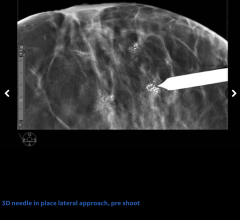

April 4, 2023 — MOLLI Surgical, the company that is pushing the boundaries of precision surgery, today announced the ...